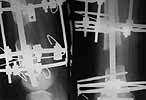

You wrote: Proximal locking screws seem to be placed outside the holes. What targeting technique was used? Why this position was accepted?

I am attaching another view. This is not a good lateral but tells me that the proximal locking is in. The holes in this SIGN nail are oval and hence shows a gap in spite of the locking screw. Proximal locking was done using free hand technique under imaging.